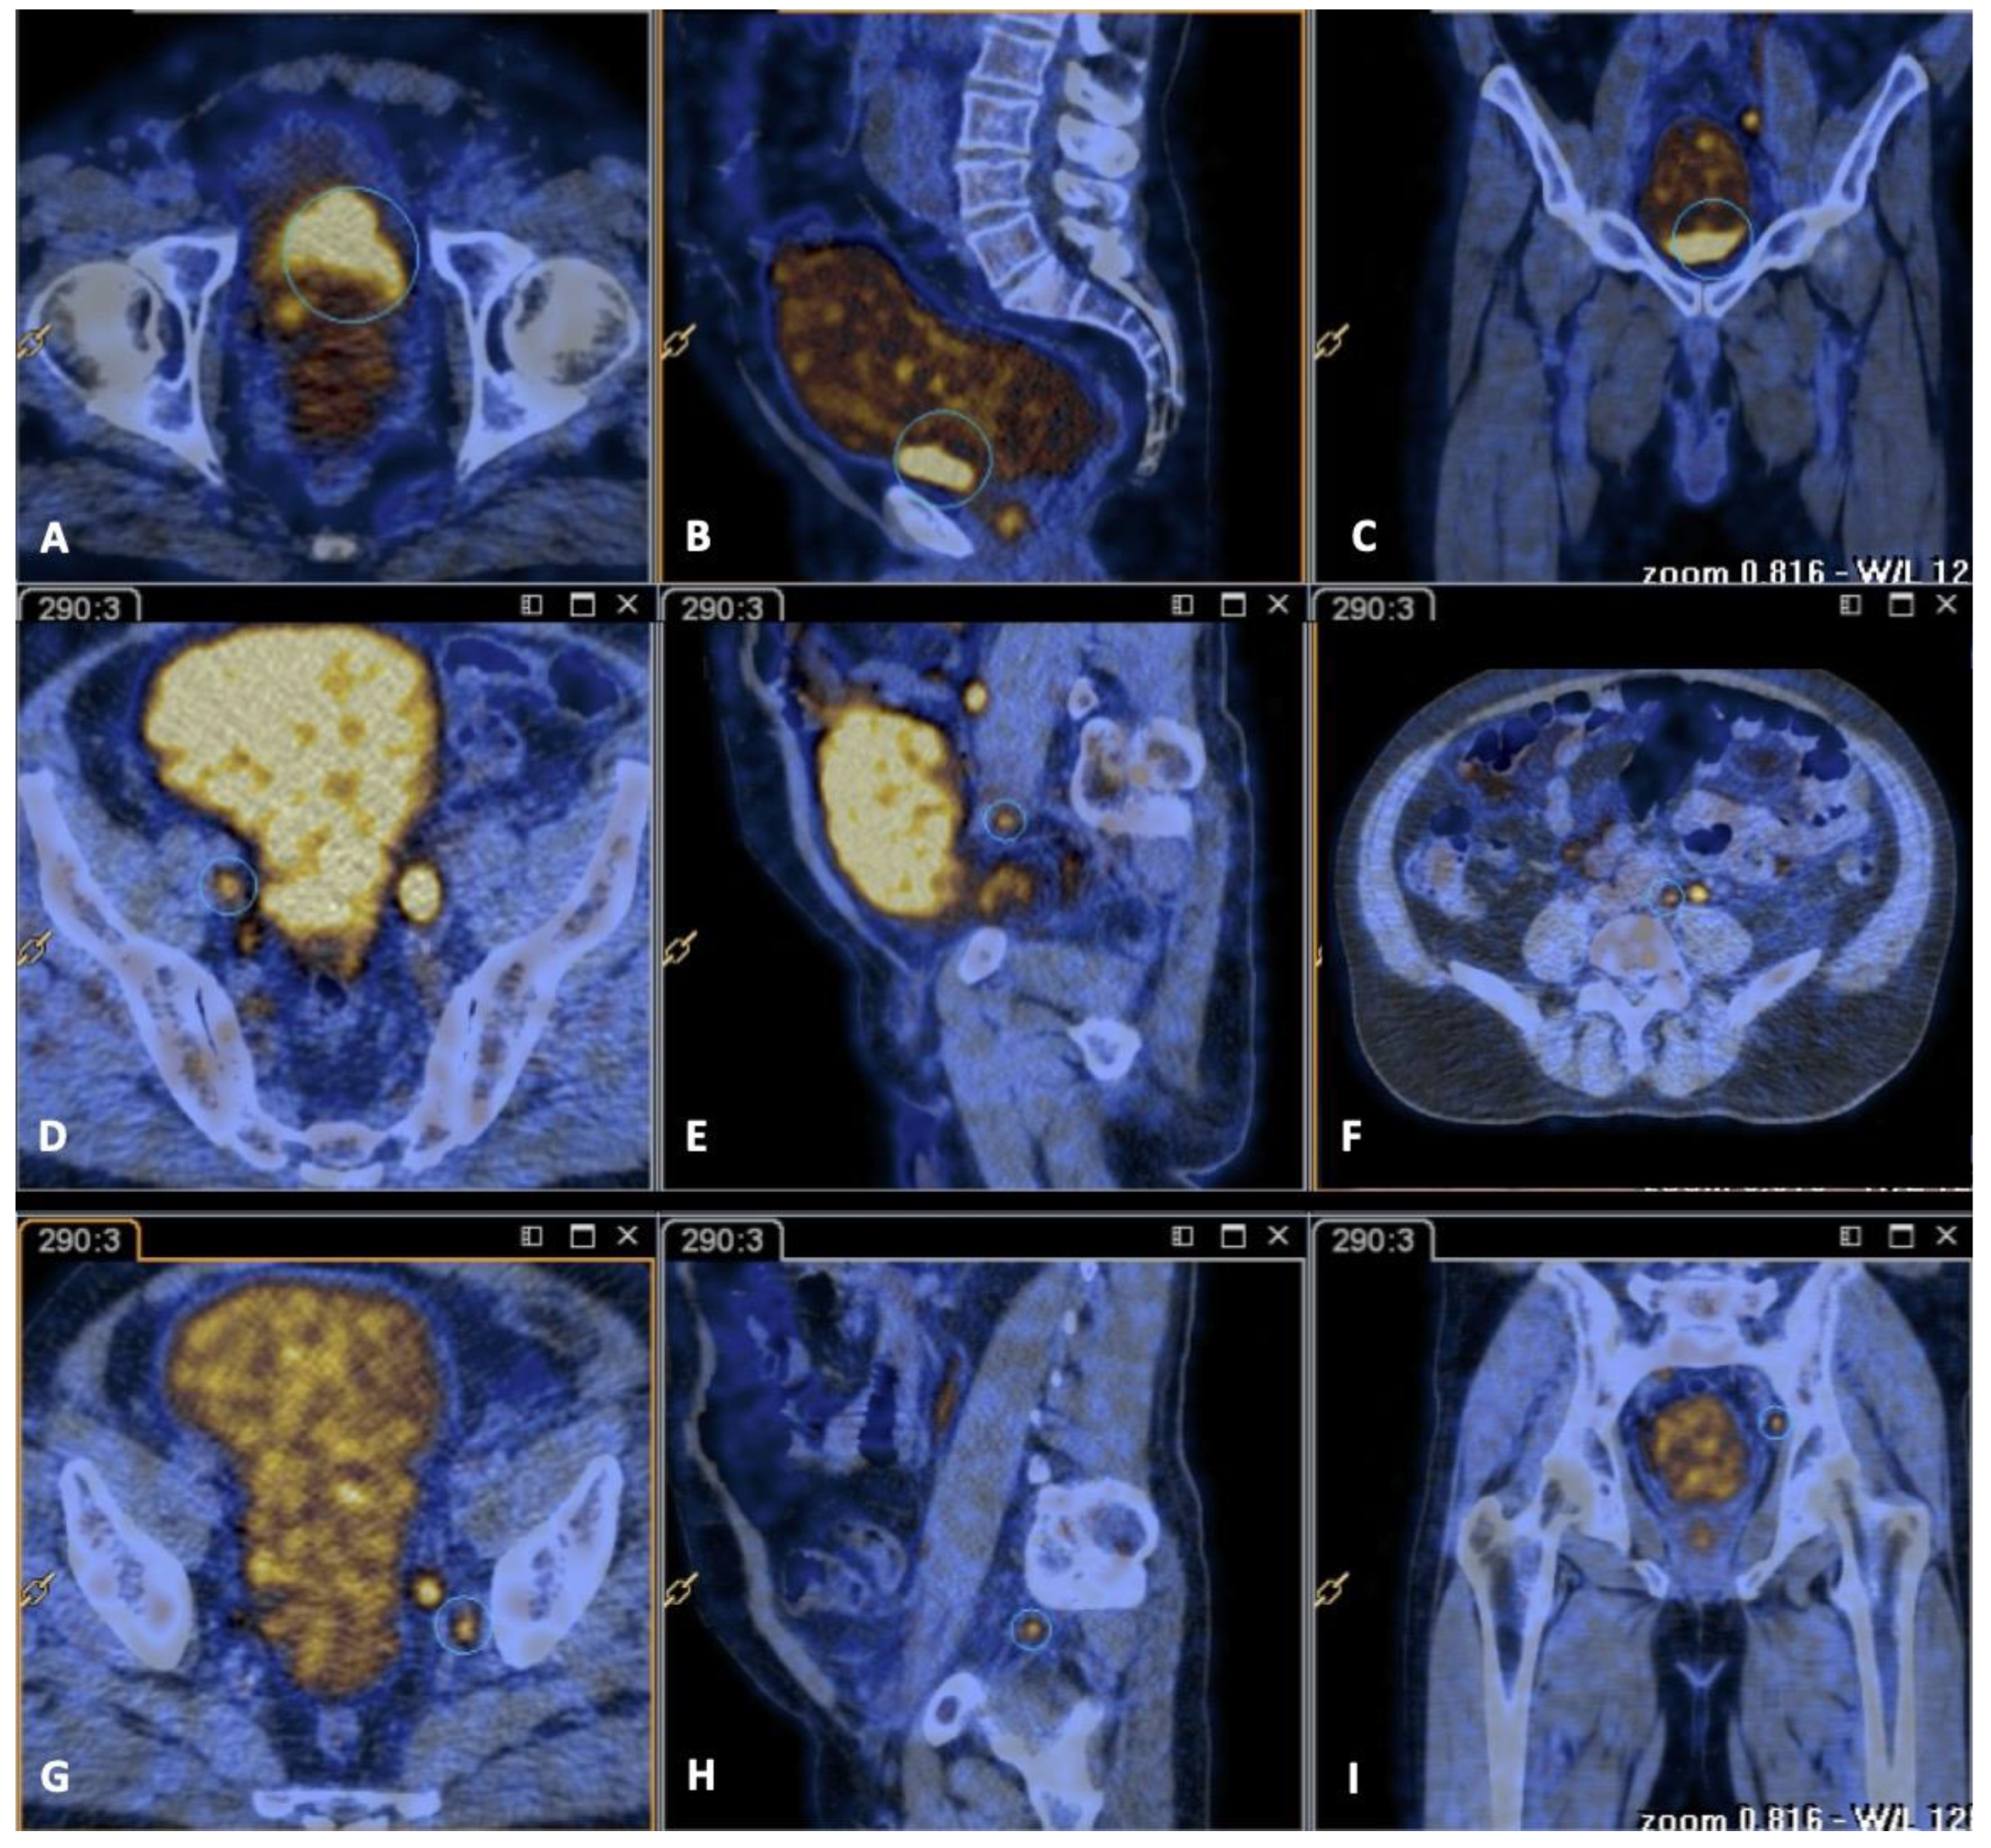

2. Case Report